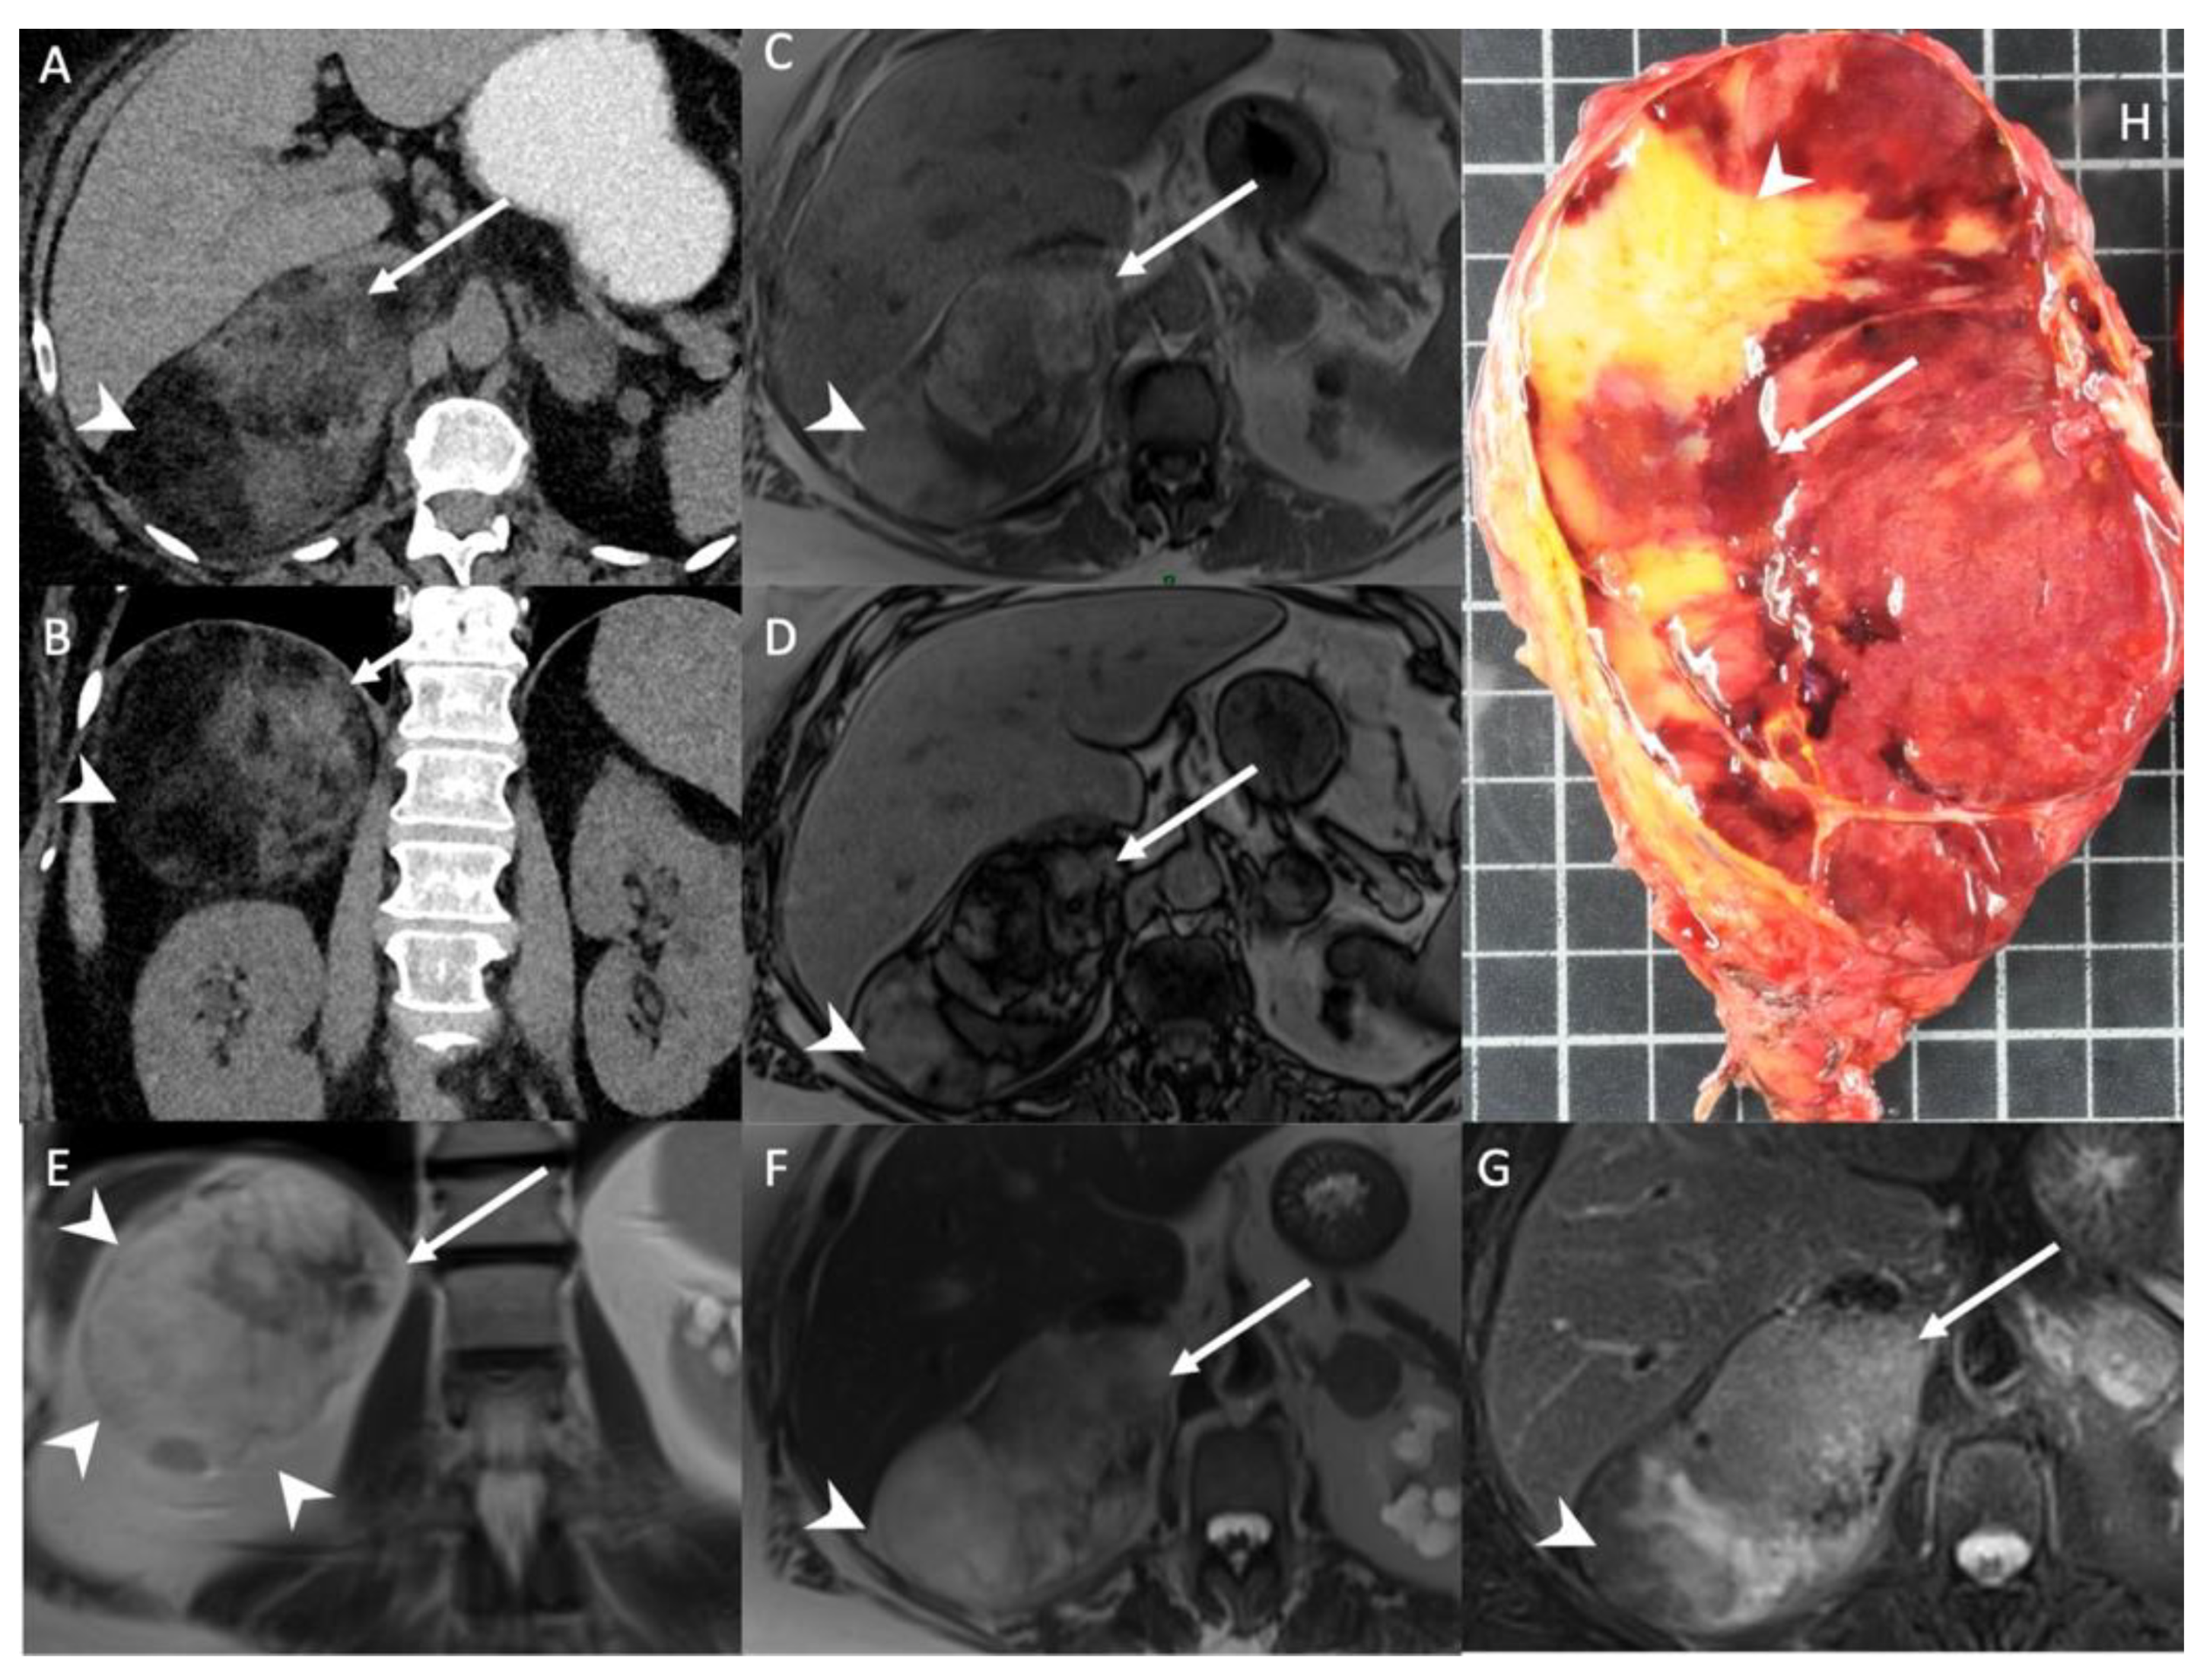

- Kedra, A.; Dohan, A.; Gaujoux, S.; Sibony, M.; Jouinot, A.; Assie, G.; Groussin Rouiller, L.; Libe, R.; Bertherat, J.; Soyer, P.; et al. Preoperative Detection of Liver Involvement by Right-Sided Adrenocortical Carcinoma Using CT and MRI. Cancers (Basel) 2021, 13, 1603. [Google Scholar] [CrossRef] [PubMed]